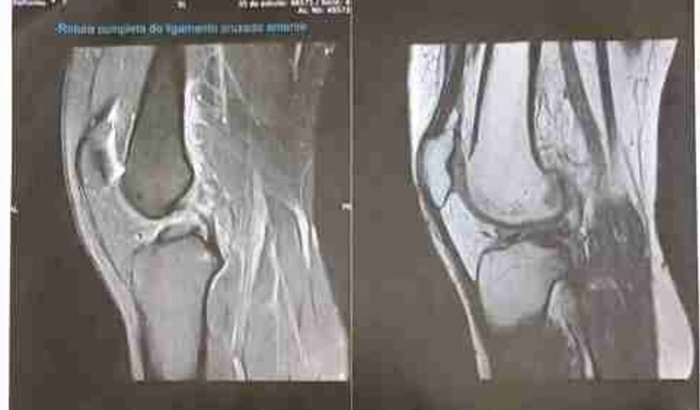

Oii gente, aqui é a Rafaela Klein, mais conhecida como Fafi. Sou atleta do Flamengo - Westfália há 13 anos, e infelizmente em março deste ano acabei me lesionando em uma partida. Houve o rompimento completo do LCA (Ligamento Cruzado Anterior), e preciso da ajuda de vocês para realizar a cirurgia o quanto antes e poder voltar a fazer o que eu mais amo, que é jogar futebol.Conto com o apoio de vocês, e desde já, agradeço 🙏🏼❤️🖤